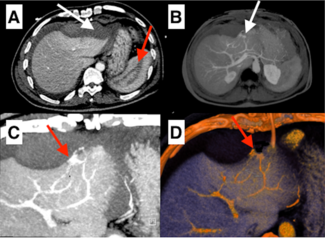

A 58-year-old male patient presented with anterior myocardial infarction after 36 hours of symptom onset. A transthoracic echocardiogram showed moderate left ventricular dysfunction (ejection fraction, 35%) and hypokinetic anteroseptum and...